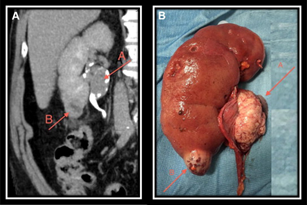

CT Urography – A computerized tomography (CT) urogram is an imaging technique used to evaluate the urinary system. It also evaluates the location of the tumour mass in the kidney and its extent of spread. The tumour can be localised within the kidney or could have spread outside the kidney. It also helps in staging of kidney cancer.

Radical Nephrectomy – is the Ideal treatment for Kidney Cancer. These may require additional chemotherapy, immune therapy etc depending of extent of the disease or the recurrence of the cancer.

Partial Nephrectomy – is the surgery for removal of entire tumour mass and preserving the healthy renal parenchyma.

Radical Nephrectomy consists of removal of entire kidney with its tumour in situ and without opening its covering (fascia) and is removed in to along with adrenal gland, surrounding fatty tissue and lymph nodes. These lymph nodes are the commonest site of spread of kidney cancers. Involvement of lymph nodes is considered as spread of tumour and increase its staging and reduces the outcome of surgery and may require other modes of therapy along with strict follow up and monitoring.

Partial Nephrectomy sometimes can be the preferred treatment for many people with a early stage of kidney cancer. This can be done to remove a single localized tumor between 4 to 7 CMS. In this surgery only the cancerous tumor is removed leaving behind the healthy kidney tissue as much as possible. Hence, this surgery is performed either in a single kidney with the tumor or where it is of utmost importance to preserve the renal parenchyma. It is important to have the tumor free margins at the periphery